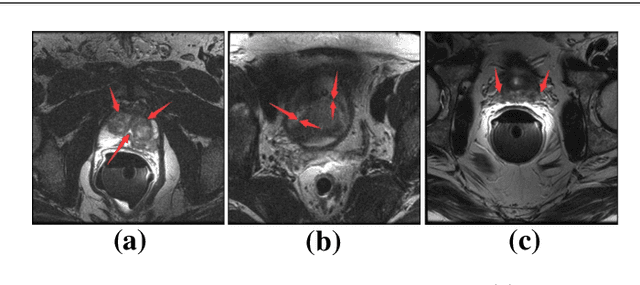

Abstract:Automated medical image segmentation plays an important role in many clinical applications, which however is a very challenging task, due to complex background texture, lack of clear boundary and significant shape and texture variation between images. Many researchers proposed an encoder-decoder architecture with skip connections to combine low-level feature maps from the encoder path with high-level feature maps from the decoder path for automatically segmenting medical images. The skip connections have been shown to be effective in recovering fine-grained details of the target objects and may facilitate the gradient back-propagation. However, not all the feature maps transmitted by those connections contribute positively to the network performance. In this paper, to adaptively select useful information to pass through those skip connections, we propose a novel 3D network with self-supervised function, named selective information passing network (SIP-Net). We evaluate our proposed model on the MICCAI Prostate MR Image Segmentation 2012 Grant Challenge dataset, TCIA Pancreas CT-82 and MICCAI 2017 Liver Tumor Segmentation (LiTS) Challenge dataset. The experimental results across these data sets show that our model achieved improved segmentation results and outperformed other state-of-the-art methods. The source code of this work is available at https://github.com/ahukui/SIPNet.